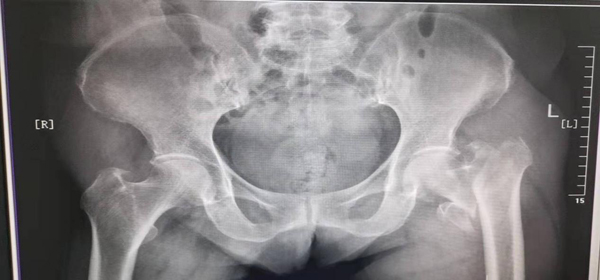

两个多月前,82岁的孙奶奶因“摔伤致左髋部疼痛伴活动受限6小时”入住陕西省核工业二一五医院创伤骨科,入院后拍X线片示:左侧股骨粗隆间骨折。查体:左下肢外旋90度,活动受限,患肢肌力可,余无明显异常。通过询问得知,孙奶奶既往30年前诊断为高血压,10年前又患脑梗死,同时合并有高血压、低蛋白血症、肾功能不全、慢性支气管炎并肺气肿等多种疾病,全身各脏器功能储备差,术中容易出现心、脑血管意外导致死亡。考虑到孙奶奶年事已高,加之其复杂的身体状况,接诊的杨萌国医生立即通知郭永良主任,并向医院上报重大手术。

术前三维CT: